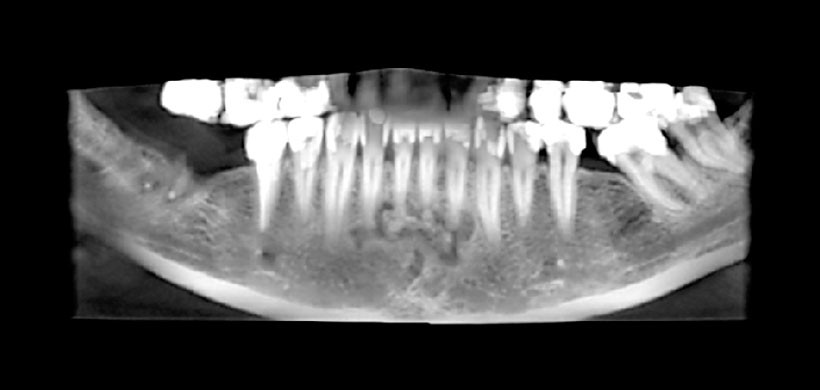

Fig 1. Reformación panorámica de la tomografía volumétrica, muestra una lesión multifocal que se extiende desde la cara medial del incisivo lateral inferior derecho hacia la parte distal del incisivo lateral inferior izquierdo.